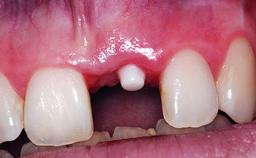

Replacement of a Missing Upper Left Central Incisor, Late Placement of an RC Bone Level Implant and Adjacent Tooth Restoration

A healthy 38-year-old male patient was referred for replacement of a failing tooth-supported cantilever fixed dental prosthesis on teeth 11 and 21. The patient reported a history of trauma at 13 years of age that had resulted in the subsequent loss of tooth 11, as well as endodontic treatment of the adjacent abutment tooth 21. A metal-ceramic cantilever fixed dental prosthesis replacing tooth 11 had been provided by his general dentist several years after the loss of the tooth, with tooth 21 as the sole abutment. At the time of initial presentation, this restoration had been in service for over 20 years.